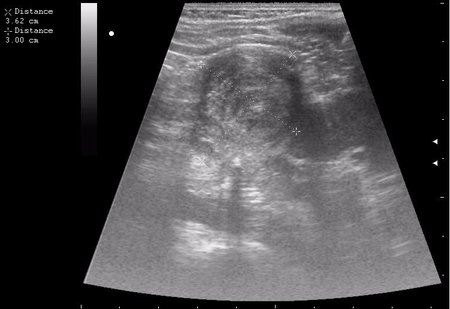

Гематома почки

нижний полюс